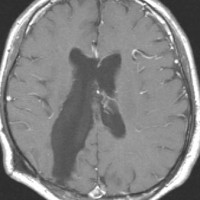

central neurocytomaが透明中隔 septum pellucidum から発生していることがよくわかる症例です。症状はありませんでしたが,この腫瘍がこのままのサイズで留まることはあり得ないので手術摘出を勧めました。これ以上大きくなると手術にしても放射線治療にしてもリスクが大きくなりすぎます。脳弓にくっつくので脳弓損傷を避けるのが手術のポイントです。脳室壁にくっつくのですが剥がしていけば取れますが,大きな上衣下静脈 large subependymal vein の損傷には注意を払います。

手術後の画像です。脳神経外科の先生は手術根 surgical track に注目して下さい,左頭頂葉皮質切開 transcortical approachで手術を行っています。このルートでは全く手術後の神経脱落症状が出ませんでした。central neurocytomaの手術方法は,上記に加えて前頭葉皮質切開でまっすぐ前角に入る方法と経脳梁法 transcallosal approachがあります。経脳梁法は限られた小さめの腫瘍にしか応用できません。anterior callosal approach以外ではdisconnection syndromeが出るからです。central neurocytomaは脳室の壁にベトベトくっつくし,anterior callosal approachでは脳室壁の観察はかなり限られるからです。大きなものでは必ず経皮質法を選択して下さい。